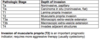

Renal Cell Carcinoma survival rate depends on?

What are 3 ways to classify RCC?

Depends on stage

Avg = 5 yrs

Kidney - 95%: Distant metastases - <10%

Grade of RCC